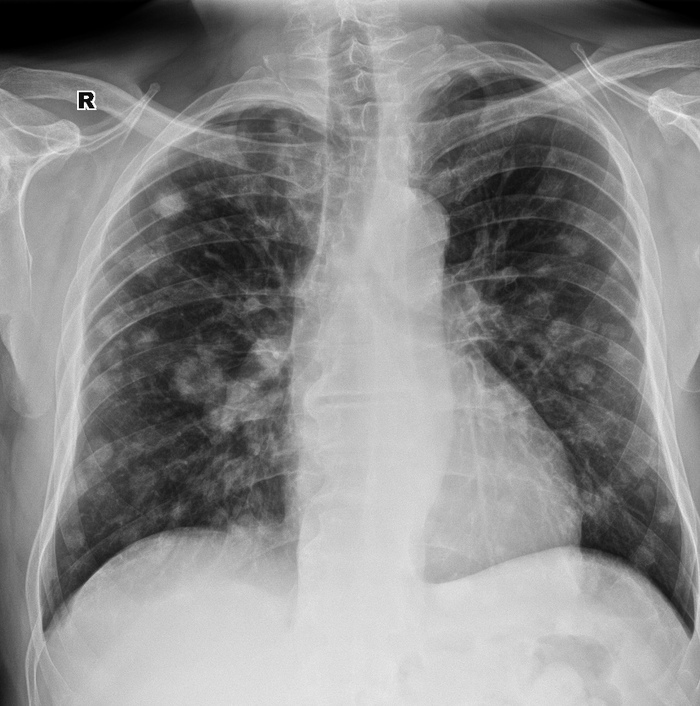

За последние 3 месяца – ухудшение самочувствия, постоянная слабость, на снимках - выраженная отрицательная динамика по сравнению с предыдущими исследованиями. Снимок от 22 марта 2018. Указывать стрелочками смысла нет, и так все видно.

Вот так, менее чем за два года жизнь относительно здорового мужчины может полностью измениться.